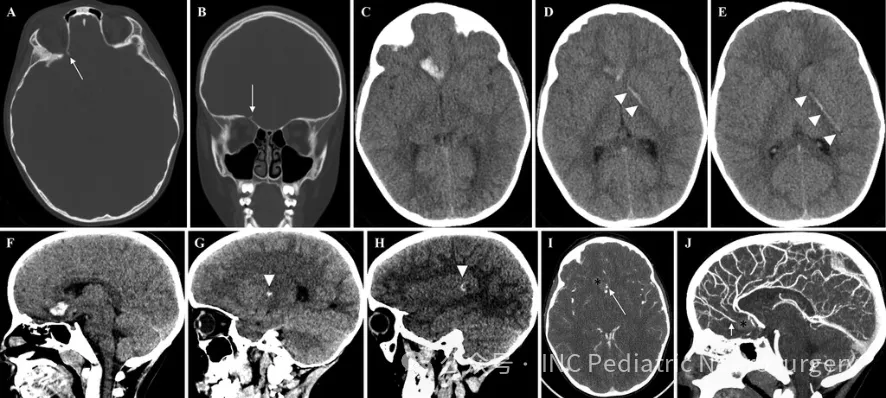

影像学检查发现

影像学检查显示:

右侧额叶脑实质出血灶向左顶叶延伸

出血路径经过胼胝体膝部、左侧苍白球、内囊前肢和左侧后部岛叶

合并右侧眶顶骨折及局灶性蛛网膜下腔出血

血管造影检查证实:

颈内动脉、基底动脉和椎动脉的颅内分支血流通畅

未见明显血管狭窄或颅内夹层形成

值得注意的是,铁杆穿透路径恰好避开大脑前动脉,勉强规避内囊后肢,最终止于对侧左侧颞上回。眼科检查显示视力正常,仅见轻微结膜下出血。